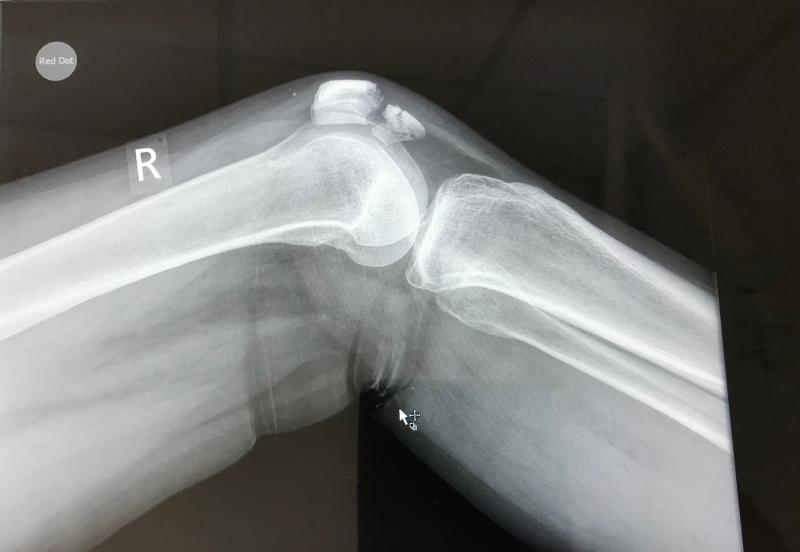

Diz protez ameliyatı sonrası süreç hakkında bilgi almak istiyorum. Ameliyatın ardından hastalar ne kadar süre hastanede kalıyor? İlk günlerde nasıl bir tedavi uygulanıyor ve hastalar ne zaman ayağa kalkabiliyor? Bu süreçte ağrı yönetimi nasıl sağlanıyor? Bu konularda deneyiminiz nedir?

Ameliyat sonrası hastalar genellikle 2 ila 5 gün arasında hastanede kalmaktadır. Bu süre, hastanın iyileşme hızına, komplikasyon riskine ve rehabilitasyon sürecine bağlı olarak değişebilir.

Ameliyatın hemen ardından, ilk günlerde genellikle fizik tedaviye başlanır. Hastalar, doktorun önerisine bağlı olarak yarım gün içinde ayağa kaldırılabilir. İlk olarak, yatakta bacak hareketleri yapılır ve daha sonra destekle yürüme çalışmaları başlar.

Hastalar genellikle ameliyattan 1-2 gün sonra, fizyoterapist eşliğinde ayağa kalkma çalışmalarına başlayabilirler. Her hastanın durumu farklı olduğundan, bu süreç kişiye özel olarak değerlendirilir.

Ağrı yönetimi için genellikle ağrı kesiciler kullanılır. Ameliyat sonrası ilk günlerde ağrılar olabilir, bu nedenle doktorun önerdiği ilaçlar düzenli olarak alınmalıdır. Ayrıca, soğuk kompres uygulamaları da ağrıyı azaltmak için faydalı olabilir.